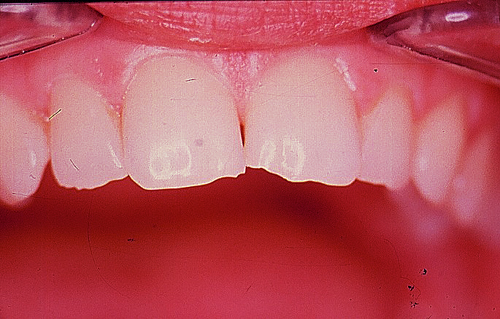

En ciertas áreas del saber humano, el lenguaje confuso o criptográfico Muchas son las técnicas elaboradas para lograr un desgaste selectivo, y numerosos autores han expuesto en su momento variadas formas de lograr una función oclusal fisiológica mediante el ajuste de la misma. Han pasado años desde entonces y, sin embargo, aún hoy, un altísimo porcentaje de profesionales “navega” por el mar de la confusión oclusal, dada la diversidad de conceptos y escuelas, sin lograr arribar a costa alguna donde poder anclar un conocimiento sólido sobre cómo tratar la oclusión Ya se esté realizando una simple obturación, endodoncia, incrustación, radectomía u ortodoncia, la lógica pocas veces, en la mayoría de los casos, vincula un tratamiento con otro, siendo el resultado final el mismo caos inicial; enmascarado por mucho tratamiento profesional. El ajuste oclusal es un medio inicial de proveer al sistema enfermo de: Dicha técnica, que puede ser terapéutica en sí misma; consta de dos etapas, a saber: 1) Ajuste Oclusal por Adición Mediante el estudio de la guía anterior, encargada de efectuar las Disclusiones durante las excursiones mandibulares, podremos observar si ésta es funcional o no. • Marcas de carácter continuo, si en ese recorrido se produce la Disclusión de los sectores posteriores y todo marcha correctamente. FIG 1-2 Si por el contrario observamos: • Marcas de carácter discontinuo, significa que dicha Disclusión se está efectuando por medio de una pieza dentaria posterior a la guía anterior. FIG 3-4-5 (FIGS. 3, 4 Y 5). En la figura 6 las flechas indican, en un caso clínico de análisis oclusal, la presencia de marcas discontinuas que indican Interferencias en Propulsiva. FIG 6-7 Y por último, si existieran: • Abrasiones de las áreas discluyentes en las áreas de diagnóstico de la guía anterior, deberemos aportar material a dicha zona para no permitir el choque lateral de las piezas posteriores (Ajuste Oclusal por Adición) En las imágenes 11 y 12 podemos observar la adición de composite en la punta de un canino derecho, previa la observación de la Faceta Parafuncional remarcada durante el análisis oclusal en el articulador. (FIGS. 8 A 12). 2) Ajuste oclusal por Sustracción o Desgaste Habiendo cumplido ya con la verificación de la funcionalidad de la Guía Anterior, comenzamos los desgastes en céntrica, a fin de lograr un único arco de cierre, guiado eficazmente por la Guía Anterior; es decir: la coincidencia entre Oclusión Habitual y Oclusión en Relación Céntrica. En este caso, intentar gastar dichos puntos, de ser posible sólo en las cúspides de corte o no fundamentales: • Crestas Triangulares Internas, Cúspides Vestíbulares Superiores • y un poco de las Crestas Triangulares Internas, Cúspides (FIGS. 13 A 16). Si la deflección es hacia el lado opuesto, se invierten los desgastes. En las migraciones hacia adelante, las únicas razones posibles están en los puntos estabilizadores (FIG. 17); es decir: -Vertientes Distales de los Rebordes Marginales, Triangulares (FIG 17) (FIG 18 A-B-C-D) Obsérvese cómo, en una boca prácticamente entera, comienzan a “desmoronarse” prismas adamantinos (FIG. 19), como consecuencia de un punto prematuro de contacto, ubicado en la posición de un estabilizador, que provoca la discrepancia horizontal postero-anterior causante de dicho efecto (FIG. 20). FIG 19-20 Dicho punto, será necesario ajustarlo antes de cualquier tratamiento en la zona ¿Cuáles serían las consecuencias si esos incisivos fueran implantados tal como es frecuente observar en múltiples congresos y cursos de implantología, donde el tema de la oclusión no es más que un cuadro polifacético y anecdótico? 14 15 16 17 Todo producto del adelantamiento mandibular Realizados ya los desgastes en céntrica, obteniendo de esta manera un único arco de cierre, es decir, oclusión en relación céntrica, debemos realizar el ajuste de las excéntricas, apoyando la acción de la guía anterior, para lo FIG 22 a. De un lado a otro de un mismo maxilar, la imagen es especular, o sea invertida. b. En hemimaxilares cruzados, la imagen es idéntica. Allí donde existan colisiones entre cúspides, se deberá crear un surco para que dicha cúspide antagonista migre a su través, tanto en el lado de no trabajo, como en el de trabajo y en el de propulsión. FIG 23 Es importante conservar esta parte del surco, ya que si no existieran, los contactos entre cúspides serían en superficie y no puntiformes (fig. 24). FIG 24 1. Obtener un único arco de cierre con coincidencia entre oclusión habitual y relación céntrica. 2. El cierre mandibular debe ser recibido sólo por la tabla premolar-molar. 3. Durante las excursiones funcionales es la guía anterior la que debe sufrir las fuerzas laterales. 4. De cumplirse estas dos premisas debemos obtener libertad de desplazamiento (no confundir con libertad en céntrica) a las piezas posteriores mediante la creación de surcos disclusivos. Examinadas ya las posibles migraciones mandibulares y los desgastes o aposiciones necesarios para poder ocluir en céntrica, es fundamental recordar que, previamente a todo tipo de ajuste, se ha hecho necesario ubicar a la mandíbula en relación céntrica. Para ello debemos utilizar el propio funcionalismo muscular 22 FIG 25 Y esto no significa otra cosa que: piezas dentarias estables en todos los planos del espacio, ATM centrada en la cavidad glenoidea, periodontos sin tensión, músculos en la dimensión de elongación adecuada para un fisiologismo Paz absoluta en la intimidad del Sistema Estomatognático. Y así, como corolario final, es posible establecer una regla de oro similar en importancia a la conocida formula: Forma = Función Ésta es: FIG 26 FUNDAMENTOS NEUROFISIOLÓGICOS DEL REGISTRO DE OCLUSIÓN EN RELACIÓN CÉNTRICA ( ORC) MEDIANTE EL USO DE LAMINILLAS DE LONG CUADRO

Esta migración generalmente se acompaña de anomalías en el sector anterior (FIG. 18).

anterior, ya que si no liberamos la causa, el efecto se seguirá produciendo y, a

pesar de que la abrasión de0estos incisivos superiores es apenas el comienzo de una futura bruxomanía, invito al lector, sea éste especialista en prótesis, operatoria dental, cirugía bucal, etc., a pensar:

Otro de los fenómenos que es frecuente observar es la respuesta

tanto del maxilar superior, “abanicando” sus piezas,

fenómeno que denominamos DISPERSIÓN (fig. 21), como del

maxilar inferior, provocando lo que los ortodoncistas durante

décadas acusaron a la erupción del 3er. molar, encimando

todo el grupo incisivo, fenómeno que denominamos APIÑAMIENTO

FIG 21